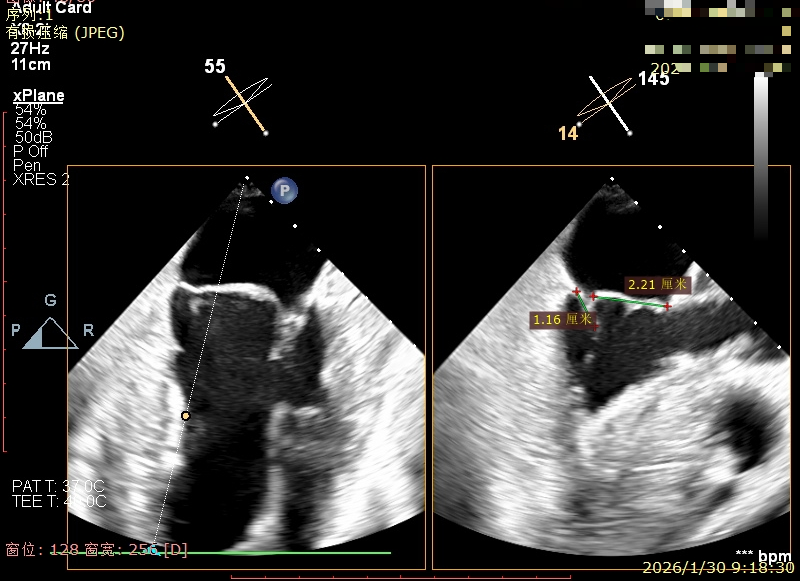

X-Plane切面切1区未见明显异常

1区上Color,未见反流来源

X-Plane切面切2区可见前叶Flail

2区上Color,可见反流来源

3区前叶长度约22mm,后叶长度约11.6mm

2区Flail Gap约4mm